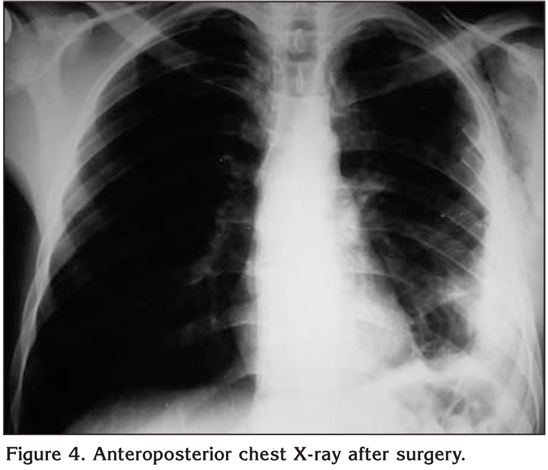

After the operation, the patient was transferred to the intensive care unit where he remained for 24 hours before being transferred to the ward. He was discharged five days after the operation. The post-operative chest roentgenogram showed no mass in the chest (Figure 4). The post-operative pathology report confirmed a Well-differentiated chondrosarcoma (Figure 5).

Figure 4